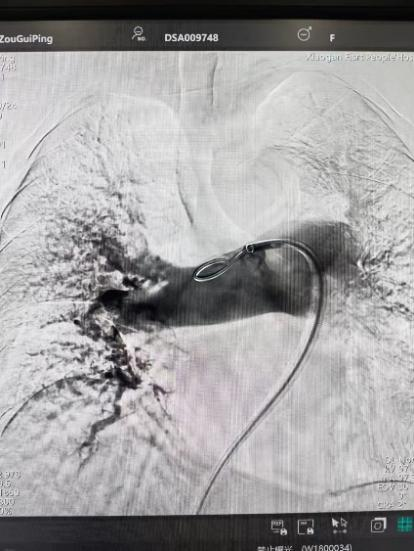

术前

术后

手术在局部麻醉下进行,团队通过股静脉穿刺,将专用抽栓导管精准送达肺动脉栓塞部位,利用负压抽吸技术成功清除大量血栓;随后,在血栓局部精准灌注溶栓药物,进一步溶解残余血栓,恢复肺部血流灌注;同时,为防止下肢深静脉血栓再次脱落引发肺栓塞,团队为患者置入下腔静脉滤器,整个手术历时约1小时。术后,邹婆婆呼吸困难症状即刻得到缓解,血氧饱和度显著提升,右心负荷明显减轻,目前身体状况正在逐步恢复中。